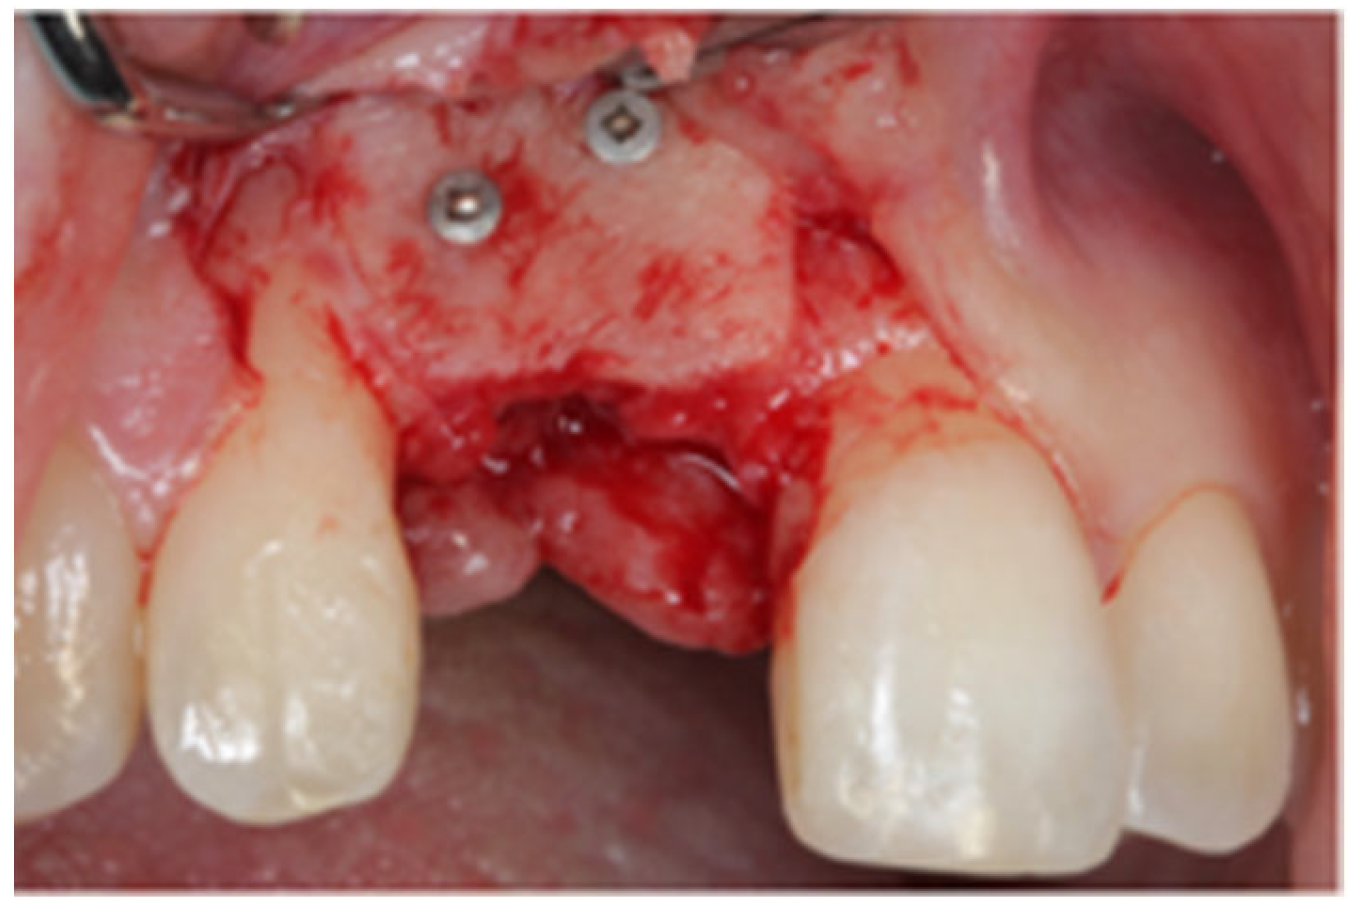

2.1. Surgical Technique